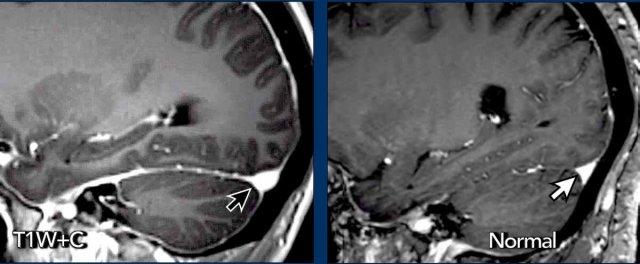

Bờ lồi của xoang tĩnh mạch ngang

Trong SIH, bờ dưới của xoang tĩnh mạch ngang có thể có dạng lồi (mũi tên đen).

Trong điều kiện bình thường, xoang tĩnh mạch ngang thường có bờ lõm (mũi tên trắng).

SIH và Dị dạng Chiari type I

Mặc dù SIH và dị dạng Chiari type I (CM1) là hai bệnh lý hoàn toàn khác nhau, cả hai đều có thể biểu hiện với đau đầu mạn tính và hạnh nhân tiểu não tụt thấp.

Ở bệnh nhân SIH, điều này có thể dẫn đến chẩn đoán nhầm thành CM1.

Hãy nghiên cứu các hình ảnh trước.

Cả hai bệnh nhân đều là phụ nữ trẻ với đau đầu mạn tính.

Bệnh nhân nào mắc SIH và bệnh nhân nào mắc CM1?

Hình ảnh

- Hạnh nhân tiểu não tụt thấp

Dấu hiệu không thật sự rõ ràng, một phần do có xảo ảnh chuyển động, nhưng hình dạng thân não không bình thường và có vẻ khoảng cách giữa cầu não và thể vú bị rút ngắn.

Có thể cũng có một số dấu hiệu ứ trệ tĩnh mạch. - Ngoài hạnh nhân tiểu não tụt thấp, hình ảnh trông bình thường.

Tiếp tục với các hình ảnh bổ sung……

- Bốn hình ảnh bên trái cho thấy các dấu hiệu điển hình của SIH với bờ lồi của xoang ngang, khoảng cách ngắn giữa thể vú và cầu não, và hình ảnh trung não bị võng xuống.

- Các hình ảnh bên phải không cho thấy các dấu hiệu này.

Bệnh nhân SIH đã được điều trị bốn lần bằng vá máu mù và đạt kết quả thành công.

Bệnh nhân Chiari type I đã được phẫu thuật giải ép vùng sọ-cổ và đạt kết quả tốt.

Đây là trách nhiệm của chúng ta với tư cách là bác sĩ chẩn đoán hình ảnh: giúp bệnh nhân SIH tránh khỏi việc bị điều trị nhầm như bệnh nhân Chiari type I.